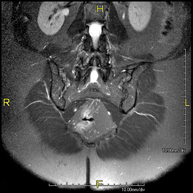

Prueba diagnóstica no invasiva que consiste en la obtención de imágenes de alta definición anatómica de la columna cervical mediante el empleo de un campo electromagnético y ondas de radio (con un emisor y un receptor). No utiliza radiación ionizante. Indicaciones: traumatismo, degeneración de la columna, hernias. - RM Columna Dorsal

Prueba diagnóstica no invasiva que consiste en la obtención de imágenes de alta definición anatómica de la columna dorsal mediante el empleo de un campo electromagnético y ondas de radio (con un emisor y un receptor). No utiliza radiación ionizante. Indicaciones: traumatismo, problemas degenerativos, hernias, tumores. - RM Columna Lumbar

Prueba diagnóstica no invasiva que consiste en la obtención de imágenes de alta definición anatómica de la lumbar y sacra mediante el empleo de un campo electromagnético y ondas de radio (con un emisor y un receptor). No utiliza radiación ionizante. Indicaciones: traumatismos, ciática, hernias discales, tumores, infecciones. - RM Sacro-cóccix